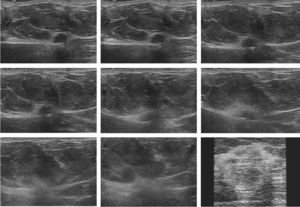

Durante el procedimiento, se producen cambios en el tejido que hay que tratar, que consisten en una progresiva pérdida de nitidez de la imagen nodular asociada a un incremento de su ecogenicidad. Finalmente, la imagen ecográfica del tumor desaparece por completo, formándose en ocasiones una masa palpable a su alrededor (fig. 3).

Serie de imágenes ecográficas obtenidas durante la ablación, tras la aplicación del electrodo de ARF. Se observa un empeoramiento progresivo de la delimitación del nódulo tumoral, acompañado de un aumento de su ecogenicidad, que finaliza con la formación de una masa palpable mal definida y de elevada ecogenicidad.